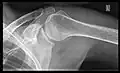

X-ray

Projectional radiography views of the shoulder include:

AP-projection 40° posterior oblique after Grashey

The body has to be rotated about 30 to 45 degrees towards the shoulder to be imaged, and the standing or sitting patient lets the arm hang. This method reveals the joint gap and the vertical alignment towards the socket.[24]

Transaxillary projection

The arm should be abducted 80 to 100 degrees. This method reveals:[24]

• The horizontal alignment of the humerus head in respect to the socket and the lateral clavicle in respect to the acromion

• Lesions of the anterior and posterior socket border, or of the tuberculum minus

• The eventual non-closure of the acromial apophysis

• The coraco-humeral interval

Y-projection

The lateral contour of the shoulder should be positioned in front of the film in a way that the longitudinal axis of the scapula continues parallel to the path of the rays. This method reveals:[24]

• The horizontal centralization of the humerus head and socket

• The osseous margins of the coraco-acromial arch and hence the supraspinatus outlet canal

• The shape of the acromion

This projection has a low tolerance for errors and, accordingly, needs proper execution.[24] The Y-projection can be traced back to Wijnblath’s 1933 published cavitas-en-face projection.[25]